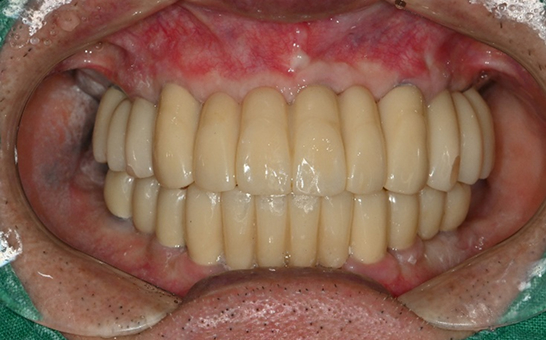

바른선택치과의원 전악 임플란트

before after

치료 시작 전 촬영 2024.01.24 | 치료 완료 후 촬영 2024.12.26

바른선택치과의원 실제 환자 전,후 사례

바른선택치과의원 임플란트 실제 사례

바른선택치과의원을 만나, 치아는 물론 삶까지 바뀌신 실제 환자분 전,후 사례를 확인하세요.

CASE 01 김** / 60대

전악임플란트

1 예후불량 치아 발치

2 발치 후 즉시 임플란트 식립 및 뼈이식

3 고정성 보철물로 수복 후 일상 회복